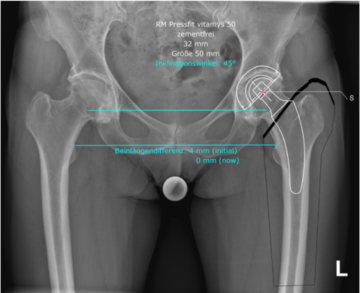

Röntgenbild im Vergleich:

Digitale Planung einer zementfreie Hüftprothese und nach der Operation

Sind meine Beine nach einer Hüftoperation gleich lang?

In der Regel sind die Beine nach der Operation gleich lang, vorbestehende Beinlängenunterschiede können fast immer ausgeglichen werden. Durch gründliche Operationsplanung (Link Bild Planung Hüfte) und operative Erfahrung werden Beinlängenunterschiede nahezu immer ausgeglichen. Um ein Auskugeln (Luxation) des Hüftgelenkes zu vermeiden, muss jedoch in einigen Fällen aufgrund der Verlängerung des operierten Beines eine gewisse Beinlängendifferenz in Kaufgenommen werden.